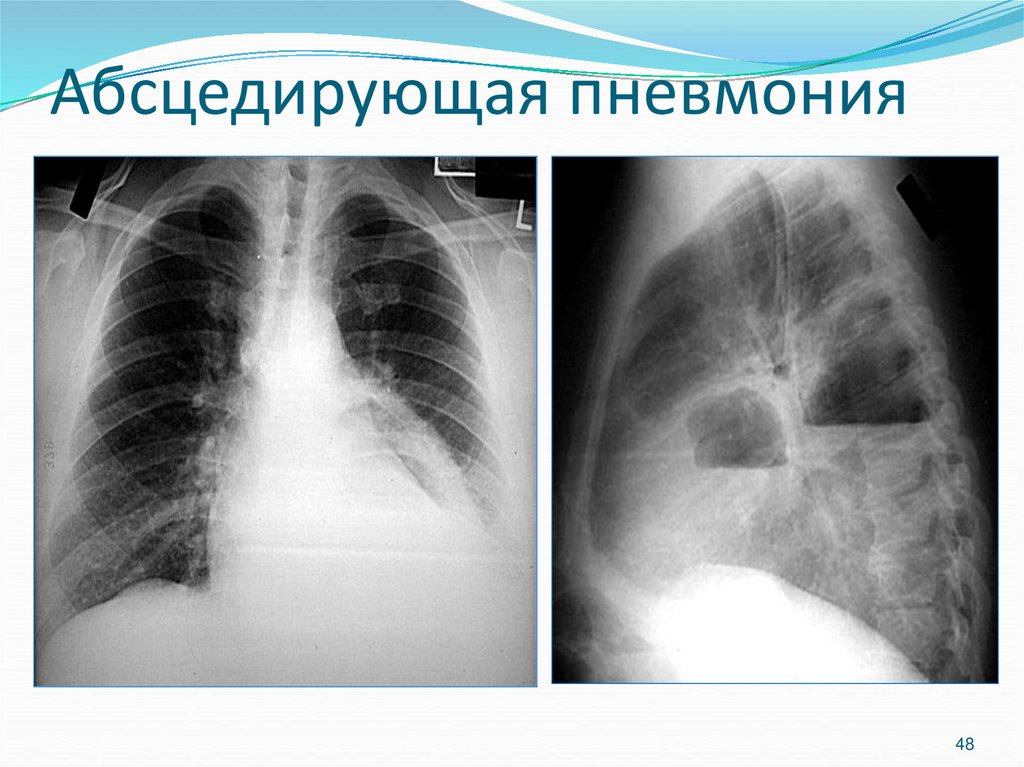

48. Абсцедирующая пневмония

48